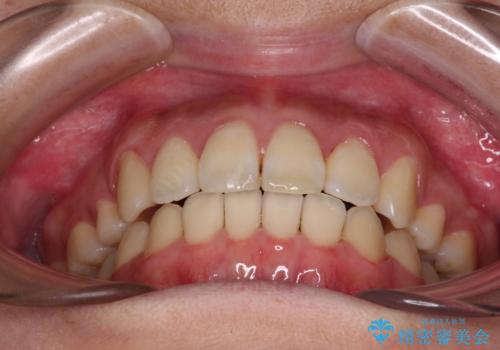

- 八重歯と叢生を気にして来院された患者様です。

上下の前歯が非接触であり、叢生や八重歯が顕著であったため、上顎左右第一小臼歯2本を抜歯して排列することとしました。

抜歯により移動量が多くなるため、ワイヤーや補助装置を活用し、その後インビザラインによる矯正治療を行うこととしました。

元々奥歯に負担のかかる咬み合わせですり減っていたため、仕上がった歯並びでも奥歯が咬んでいないように見えましたが、実際にはしっかりと咬合しており、患者様本人も咬んだ感触に違和感はないとのことでした。